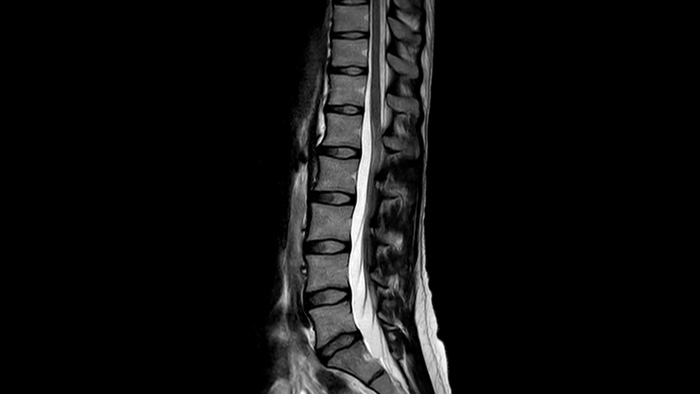

Ahora puede tenerlo todo con Ingenia Ambition. Ofrece la oportunidad de mejorar sus imágenes de resonancia magnética en todos los niveles.

Velocidad Realice exámenes de resonancia magnética hasta un 50% más rápidos2, para que pueda emplear su tiempo de manera inteligente.

Comodidad del paciente Proporciona una reducción de hasta un 40% en las apneas, con una calidad de imagen prácticamente igual. 3

Confianza diagnóstica Ofrece una resolución espacial hasta un 60% más alta en el mismo tiempo de escaneo. 4

Ahora puede tenerlo todo con Ingenia Ambition. Ofrece la oportunidad de mejorar sus imágenes de RM en todos los niveles.

Velocidad Acelere sus exámenes hasta un 50% con una calidad de imagen prácticamente igual2

Confianza diagnóstica Amplíe su capacidad de obtener imágenes excelentes en todas las áreas clínicas. Vea cómo se benefician sus compañeros.